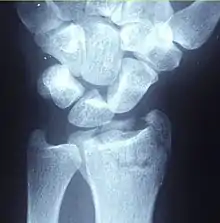

| A Colles fracture as seen on X-ray: It is a type of distal radius fracture. | |

A distal radius fracture, also known as wrist fracture, is a break of the part of the radius bone which is close to the wrist.[1] Symptoms include pain, bruising, and rapid-onset swelling.[1] The ulna bone may also be broken.[1]

In younger people, these fractures typically occur during sports or a motor vehicle collision.[2] In older people, the most common cause is falling on an outstretched hand.[2] Specific types include Colles, Smith, Barton, and Chauffeur's fractures.[2] The diagnosis is generally suspected based on symptoms and confirmed with X-rays.[1]